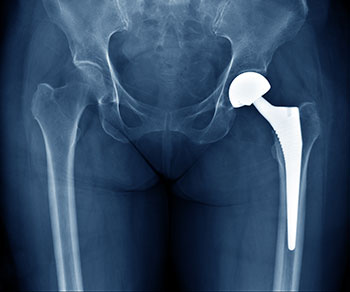

This clinical practice guideline is intended for use with adult patients (ages 18 years and older) who have been diagnosed by a trained healthcare provider with osteoarthritis of the hip and are undergoing treatment.

Total Hip Arthroplasty Toolkit